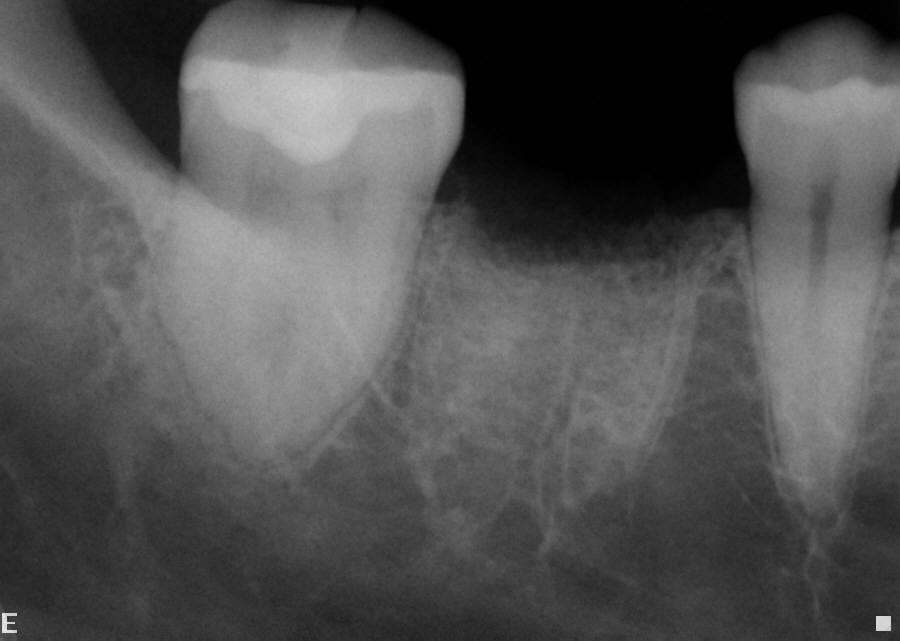

Fig 2. Example of a single-wall defect.

Figure 2

The ideal scenario for a socket preservation graft would be a single-wall defect, resulting from the atraumatic extraction of the tooth without any significant damage to the surrounding hard and soft tissues. In a single-wall defect, the only wall missing is the tooth itself, or the “roof” of the socket, resulting in an intact “bowl,” which greatly increases the success of the socket preservation procedure. This is the most common defect when performing the extraction of a single tooth (Figure 2).